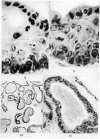

Images in this article